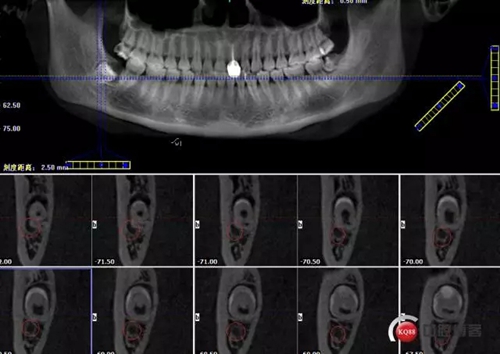

1498615726_560454.png

牙齒中1/3神經(jīng)管偏頰側(cè)